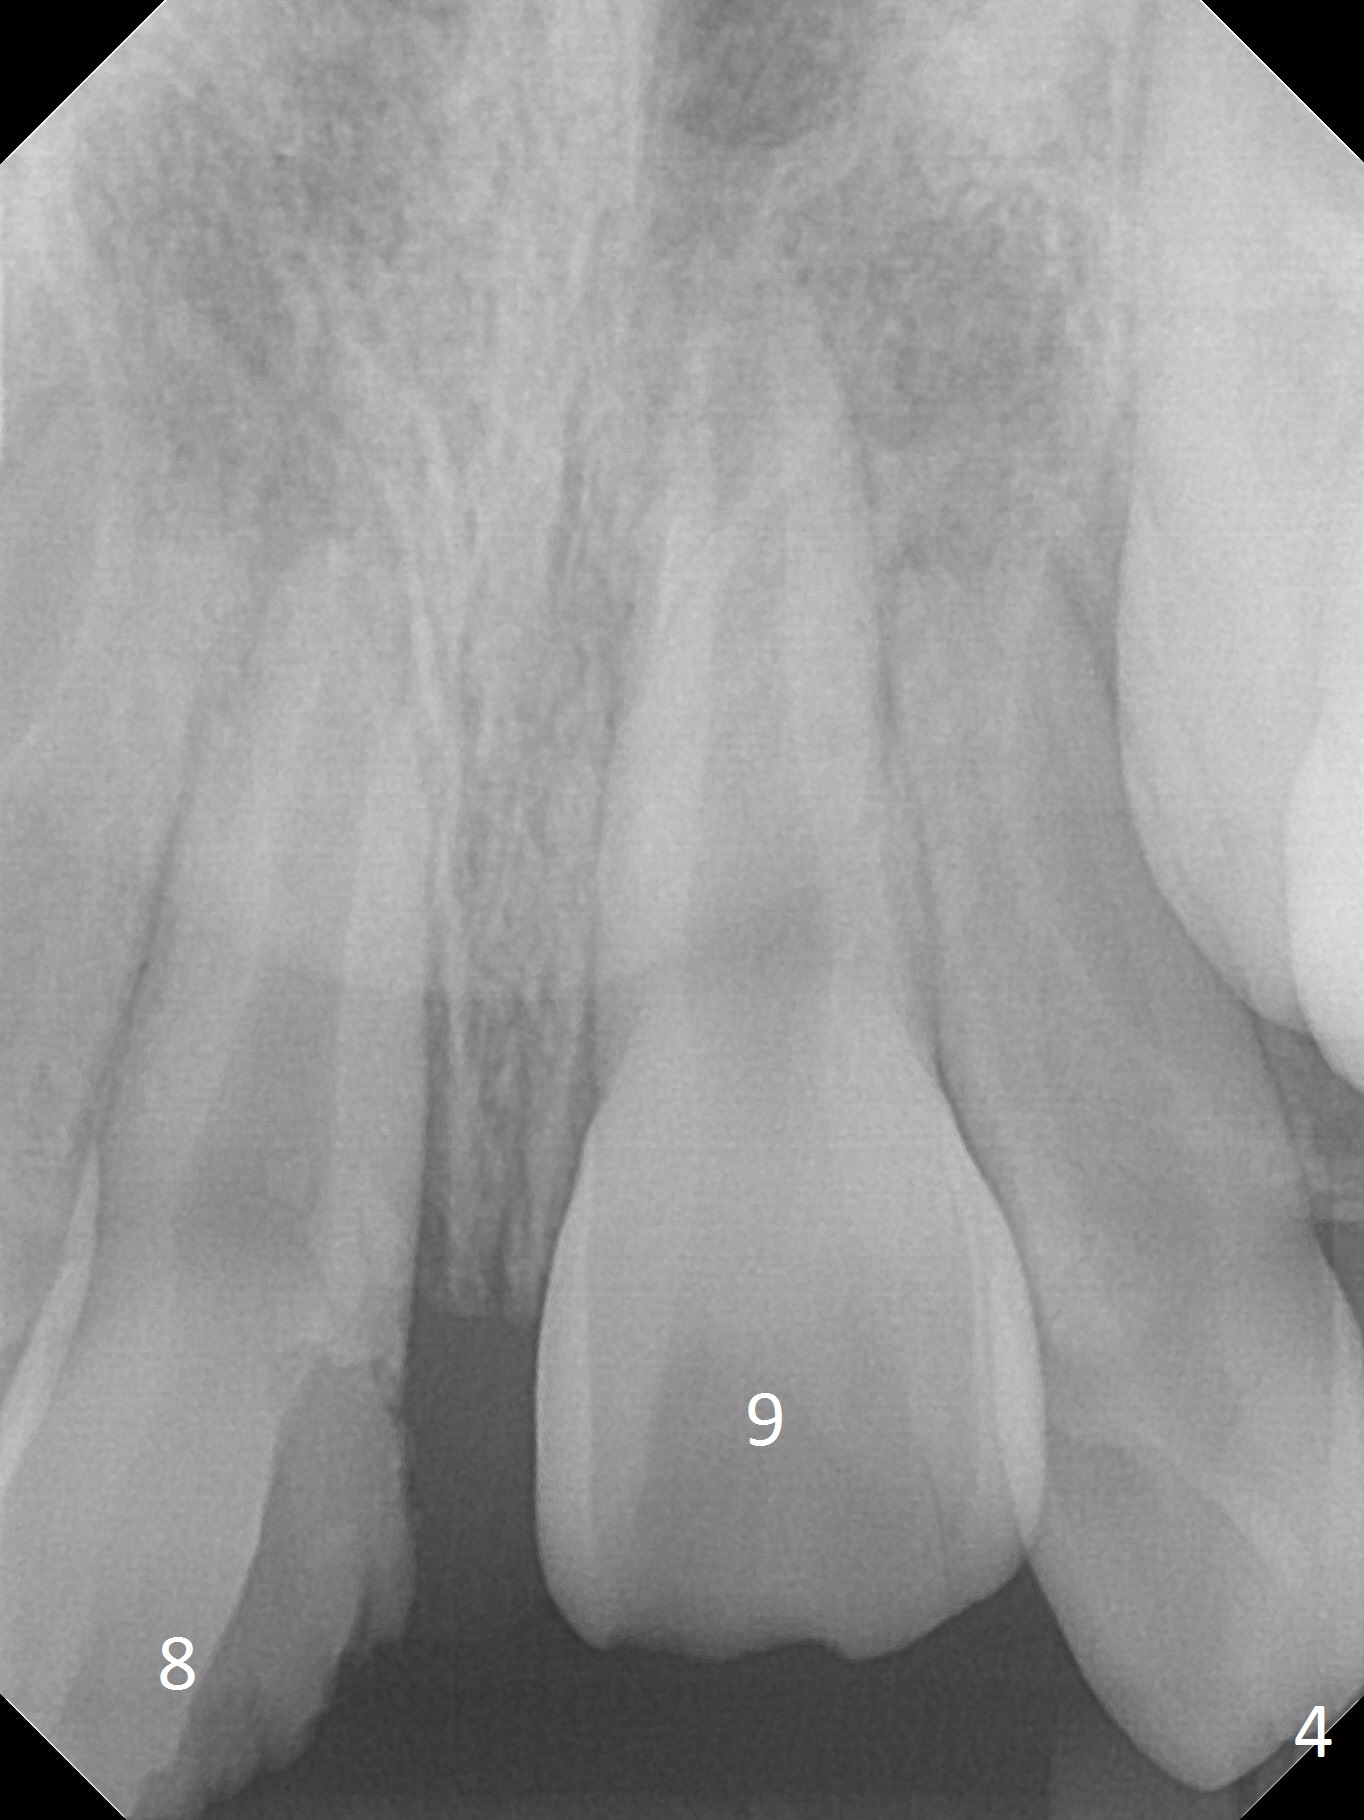

A 10-year-old boy has had Class II Division II malocclusion (Fig.1 impression taken 1 year earlier). He is brought to clinic the 2nd day after a bike accident. The tooth #8 fractures (Fig.2-4) with mesial pulpal horn exposure (Fig.3 *, while #9 intrudes. After debridement of the affected teeth (Fig.5), the exposed pulpal tissue is resected (partial pulpotomy to keep the tooth vital to finish root and apex development) and the pulpal horn is filled by MTA at #8 (Fig.6 *). The tooth #8 is restored with composite (Fig.7 C). Forceps fail to extrude the tooth #9. His parents are reluctant to accept orthodontic extrusion, which is accomplished by Dr. Shaughnessy 2 days later (Fig.8,9). The patient will leave for China in 2 days and will return in a month.

Pulpal test will be conducted for the affected teeth periodically. Complete pulpectomy will be performed with application of MTA or Calcium Hydroxide to prevent root resorption.